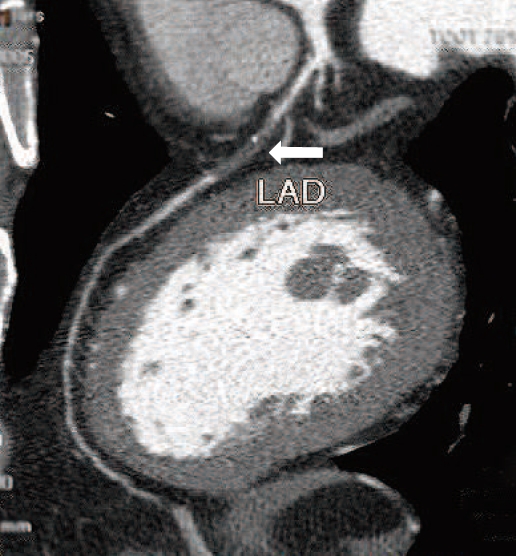

56歲男性,左半身多年前曾因中風輕癱,由於偶有心窩悶痛,各項檢查無法排除有冠心病機會,故由醫師轉來影像醫學部,進行「冠狀動脈電腦斷層血管攝影術(CCTA)」檢查。結果發現左前降枝中段一小段完全阻塞(如下圖1),心臟科醫師立即安排心導管檢查並安裝支架,解除了日後可能有心肌梗塞的危機。

圖1:CCTA發現左前降枝中段一小段完全阻塞(箭號處)